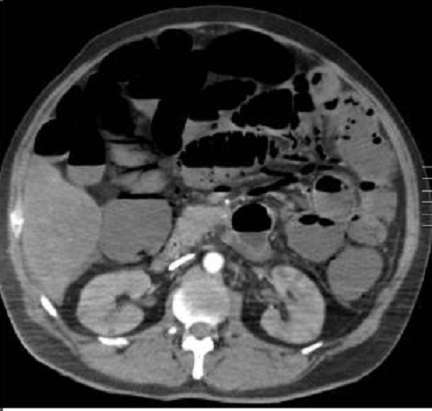

Image radiologique TDM de

ischemie mesenterique arterielle aigue : Image

de dilatation et de fine de paroi de l'intestin .

Aspect de pneunomatose parietale intestinale

est en presence . Coupe TDM axiale |